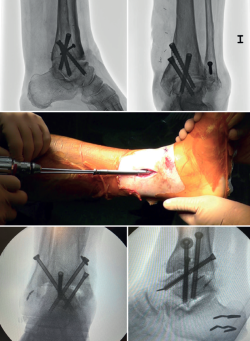

En las artrodesis de tobillo por vía artroscópica, el uso de tornillos a compresión colocados de forma percutánea es la técnica de elección (Figura 5).

La mayoría de los autores consideran el uso de tornillos canulados (de 3 a 4) como el método idóneo de fijación. Los diámetros de los tornillos escogidos oscilarán entre los 6 y los 7 mm. Con esta técnica se consigue del 85 al 100% de fusión y entre el 84 y el 95% de satisfacción del paciente(19).

Van Dijk, Kerkhoffs et al.(20) reportan excelentes resultados con el uso de 3 tornillos como método estandarizado para las artrodesis de tobillo.

Es decir, en las artropatías con componente de varo empezaríamos por un tornillo lateral, mientras que en las desalineaciones en valgo la recomendación es colocar el primer tornillo desde medial. El segundo tornillo debería ser del lado opuesto al primero. Ambos deben realizar la compresión adecuada entre superficies articulares(17).

En general, se utilizan un mínimo de 3 tornillos. El tercer tornillo es el denominado home run, cuya importancia destacan en su trabajo Holt et al.(21). Se dirige cruzando el tobillo desde la parte posterior de la tibia hasta el cuello del astrágalo. Puede utilizarse un cuarto tornillo a modo de aumentación del primero, del que contrarresta la deformidad principal.

Goetzmann et al.(22), en su serie de revisión de 111 casos, respaldan el uso de al menos 3 tornillos para la fijación de la artrodesis tibioastragalina artroscópica. Añadir un tercer tornillo parece asociarse con un menor riesgo de pseudoartrosis y un menor tiempo de consolidación. Estos efectos pueden atribuirse a una mayor estabilidad del constructo.

Glick, Myerson(23) et al. publicaron que la configuración que conferiría mayor rigidez a la osteosíntesis es con 2 tornillos desde medial y 1 desde lateral.

Se toman radiografías definitivas anteroposterior, de mortaja, lateral del tobillo, dorsoplantar y oblicua del pie para confirmar la correcta reducción, la posición y la longitud de los tornillos, en especial del tornillo home run (Tabla 3).